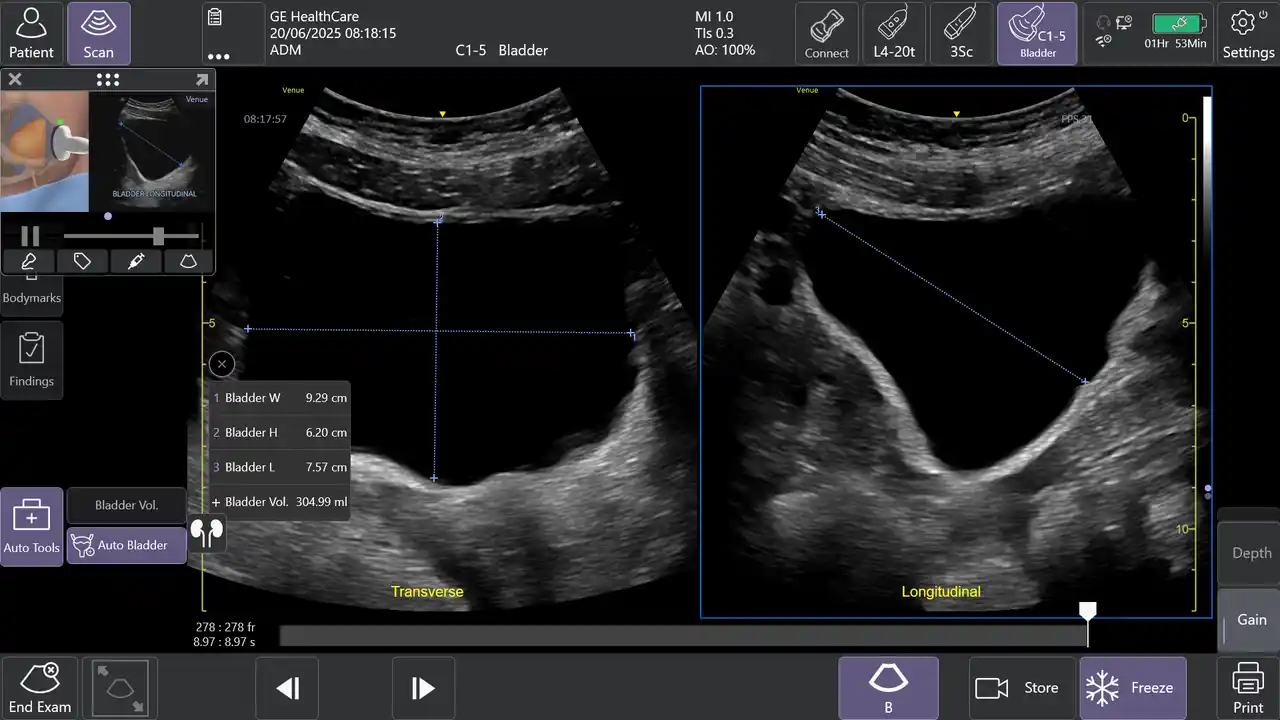

2.AIツールAuto Bladder Volume(オートブラッダーボリューム)で膀胱評価を効率化 |

AIを用いて開発されたAuto Bladder Volumeは、膀胱の容積を半自動で計測するツールです。横断像および縦断像の2方向の画像から、AIが自動的に膀胱形状を認識し容積を算出するため、再現性の高い評価が可能になります。 |

救急外来や集中治療室、手術後、病棟など様々な場面での活用が想定され、侵襲的な処置を行う事なく迅速かつ効率的な膀胱容積評価が可能となります。 |

Auto Bladder Volumeにより2断面から半自動的に膀胱容積を計算 |